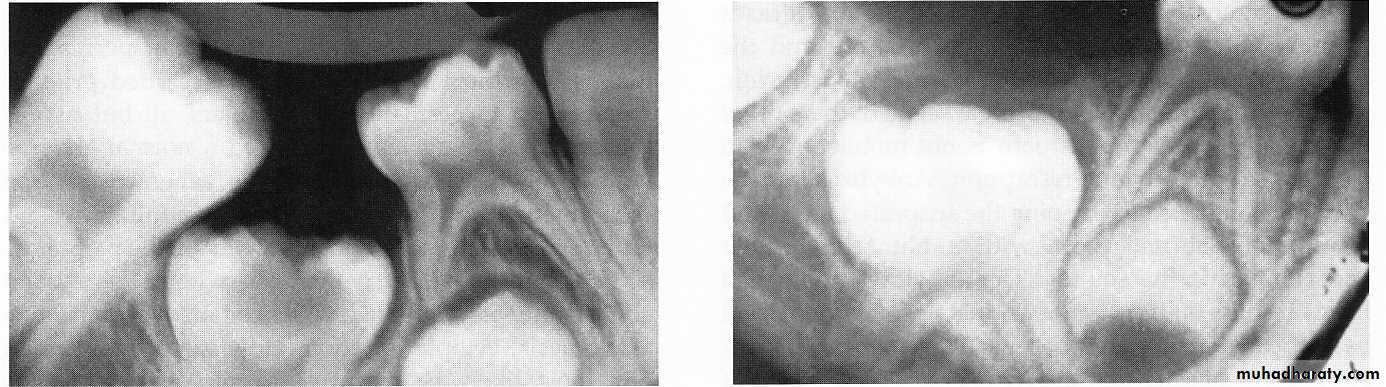

LOCAL FACTORSANKYLOSED TEETH

It is an interruption in the rhythm of eruptiona patient who has one or two ankylosed teeth is more likely to have other teeth become ankylosed.

The problem of ankylosed primary molars deserves much attention by dentists.

the ankylosed tooth is in a state of static retention, whereas in the adjacent areas eruption and alveolar growth continue and the tooth will be infra-occlussionThe mandibular primary molars are the teeth most often observed to be ankylosed

Infra-occlussion

theoriesAnkylosed second primary molar with a carious lesion in the occlusal surface.

This tooth probably becameankylosed soon after root resorption began.

An ankylosed, deeply embedded second primary molar. Surgical removal of this tooth is indicated

early ankylosis of a mandibular second primary molar that was not diagnosed until the patient was 10 years of age; at that time the succedaneous second premolar was lying malposed “

Surgical removal of this tooth is indicated

The second primary molar is ankylosed and below the normal plane of occlusion.

There is evidence of root resorption and deposition of bone into the resorbedareas.